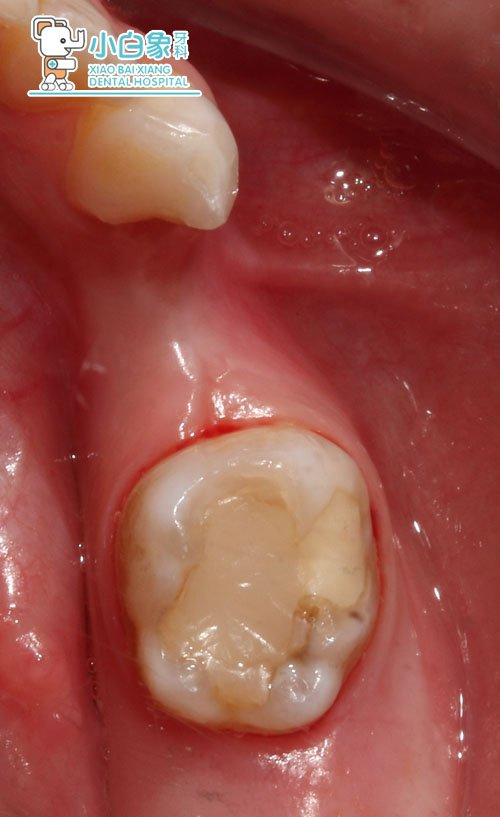

检查:74缺失,牙龈无红肿,龈合距尚可。75合面见大面积牙体色材料,叩(-),牙龈无红肿。

诊断:74早失

治疗方案:74间隙保持器

治疗过程:75试戴预成冠,取模,制作间隙保持器。

治疗过程: 一周复诊,试戴,隔湿干燥粘结。